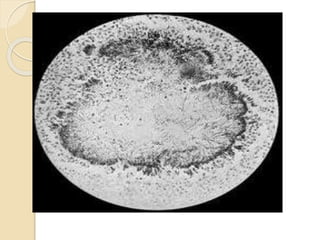

c/s brain,heart infection agar37 c 95% nitrogen 5 % co2 incubate aenerobically organism within 24h israile filaments spiderlike growth

diagnosis microscopic examination with appropriatestain c/s of purulent discharge actinomyces irregular non spore forming non acid fast non moblle gram +ve bacillus c/s aerobic non aerobic